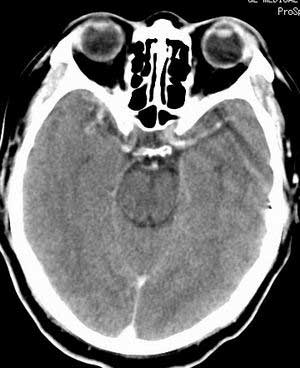

患者男,58岁。耳爆震伤后耳聋2年余,而后双耳道肿胀,间断性流脓。近一月来头痛、恶心、呕吐,右眼红痛,不能入眠。

在平扫时,见右侧枕骨下方小脑半球表面带状模糊稍高密度影,考虑为耳源性脑内感染。

平扫右侧岩骨与枕骨交角内侧脑质内见淡片状密度增高影,内缘清晰。增强图象上未见明显显示。

考虑:1)伪影可能,建议复查头ct平扫。

2)加照头ct骨窗,以显示乳突气房内是否有病变。

右枕颅骨内板下高密度应该是窦的变异,和其症状应该无关,根据病史另找原因吧。[em16]

条状高密度为小脑幕吧

条状高密度为小脑幕